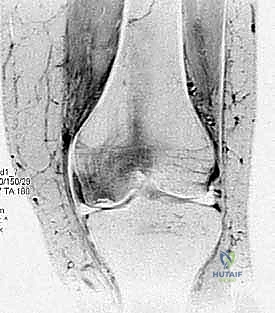

2. التصوير بالأشعة السينية (X-rays)

هي الخطوة التصويرية الأولى والأساسية. يطلب الدكتور هطيف صوراً بوضعيات محددة (أمامية خلفية، جانبية، وضعية النفق Notch view، ووضعية شروق الشمس Skyline view) أثناء الوقوف (تحميل الوزن). تساعد الأشعة السينية في رؤية العيوب العظمية، وتحديد حجم الآفة، واكتشاف أي أجسام حرة (Loose bodies) متكلسة داخل المفصل.